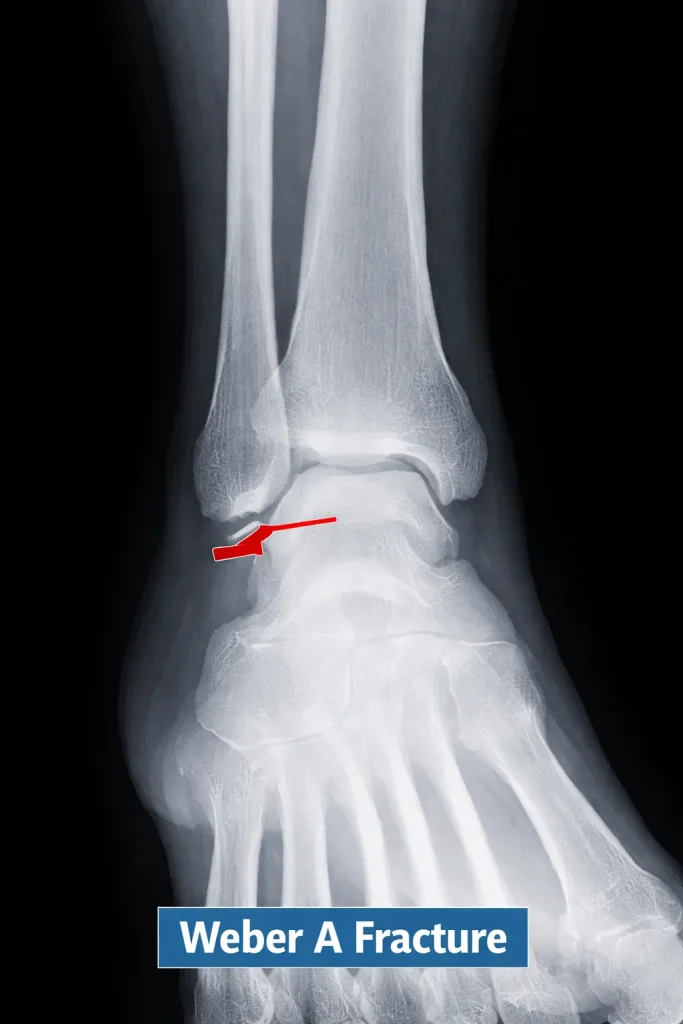

Weber A Fracture

A Weber A fracture occurs below the level of the syndesmosis. These fractures are typically stable because the syndesmotic ligaments remain intact.

Radiology Findings

- Fracture line below the ankle joint

- Syndesmosis intact

- No talar shift

Most Weber A fractures heal without surgery and have good outcomes.